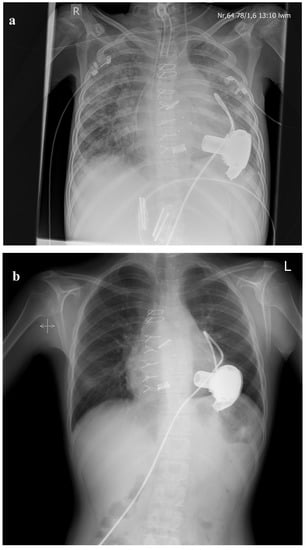

- Bauer, A.; Khalil, M.; Schmidt, D.; Bauer, J.; Esmaeili, A.; Apitz, C.; Voelkel, N.F.; Schranz, D. Creation of a restrictive atrial communication in pulmonary arterial hypertension (PAH): Effective palliation of syncope and end-stage heart failure. Pulm. Circ. 2018, 8. [Google Scholar] [CrossRef] [PubMed]

- Schranz, D.; Akintuerk, H.; Voelkel, N.F. ‘End-stage’ heart failure therapy: Potential lessons from congenital heart disease: From pulmonary artery banding and interatrial communication to parallel circulation. Heart 2016, 103, 262–267. [Google Scholar] [CrossRef] [PubMed]